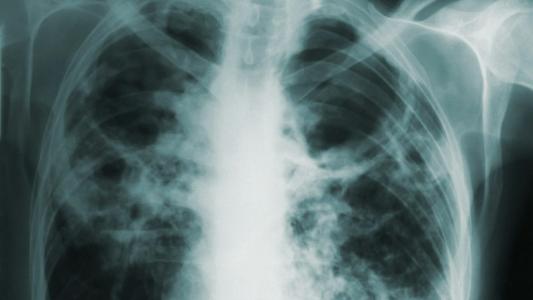

How did we come to live so many years in poor health — about a sixth of our lives, according to a recent analysis of the latest data from the IHME’s Global Burden of Disease study? It’s partly a side effect of medical advances. In 1915, almost everyone died from infectious diseases. With many of these — polio, tuberculosis, smallpox, etc. — now thwarted by vaccines, antibiotics, and sanitation, we’re able to grow older, where our bodies are more vulnerable to frailty and disability. Medical intervention can also now save us from conditions that meant certain death in the past — such as serious injury, heart attack, or cancer. However, survivors are often hobbled and unhealthy, unable to maintain their previous lifestyles.

But the primary reason for the lifespan-healthspan gap is the rise of chronic disease fueled by unhealthy lifestyle choices. Cardiovascular disease, obesity, diabetes, and chronic respiratory conditions account for 80% of chronic disease-related mortality. And long before they result in death, they seriously erode sufferers’ quality of life, sap productivity, and eat up healthcare resources.